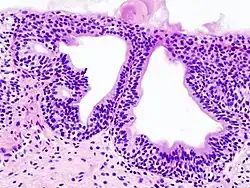

Cystitis glandularis is the transformation of mucosal cells lining the urinary bladder. They undergo glandular metaplasia, a process in which irritated tissues take on a different form, in this case that of a gland.[1] The main importance is in the findings of test results, in this case histopathology. They must distinguish a benign metaplastic change from the cancerous condition urothelial cell carcinoma.[2] It is a very common finding in bladder biopsies and cystectomies, and most often found in the trigone area. Cystitis glandularis lesions are usually present as small microscopic foci; however, occasionally it can form raised intramucosal or polypoid lesions. The cystitis glandularis lesions are within the submucosa.

There are two main types of cystitis glandularis, non-mucinous and mucinous (intestinal). The difference is in the cellular production of mucin, a normal feature of colonic and intestinal epithelial cells but not of urothelial cells.[3] Another distinction is made between focal areas and diffuse involvement of the bladder. Whereas focal areas are more common, diffuse involvement is seen in chronically irritated bladders, such as in paraplegics or those with bladder stones or indwelling catheters. Individuals with diffuse intestinal-type cystitis glandularis are at increased risk for developing bladder cancer.

Cystitis glandularis arises from and merges with Von Brunn's nests, which are groups of urothelial cells (cells of urinary tract) within the lamina propria and submucosa, formed from budding from the surface mucosa. They are considered normal. Cystitis cystica is a similar lesion to cystitis glandularis, where the central area of the Von Brunn's nests have degenerated, leaving cystic lesions. Other metaplastic entities in the urinary bladder include squamous metaplasia and nephrogenic adenoma.